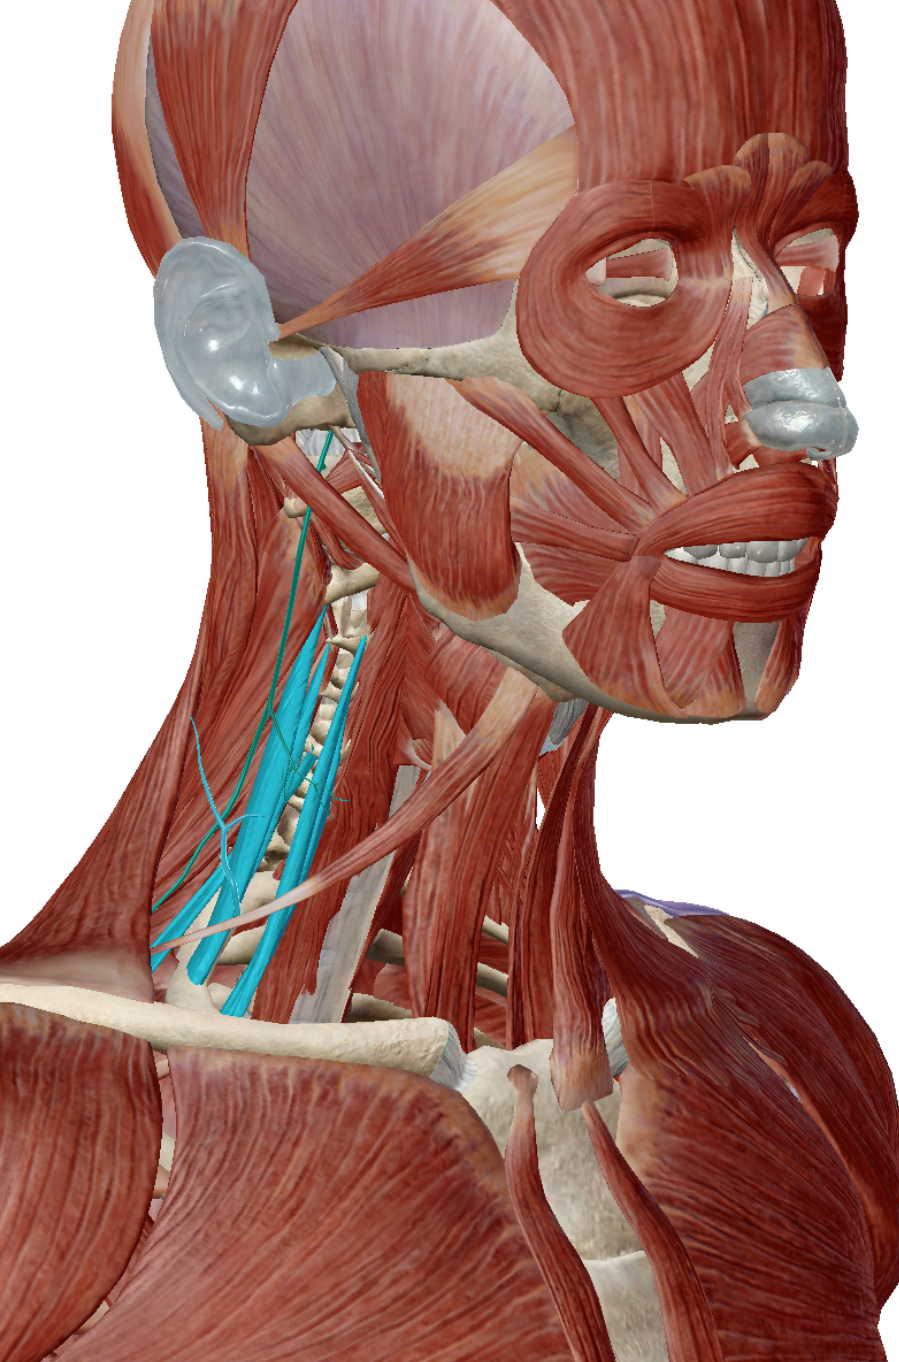

画像で青くなっているのが斜角筋です。

この筋は、全斜角筋、中斜角筋、後斜角筋とありますが、ここではすべて青く表示してあります。

画像を見てもらえばわかりますが、斜角筋は頸部に付着する小さな筋です。